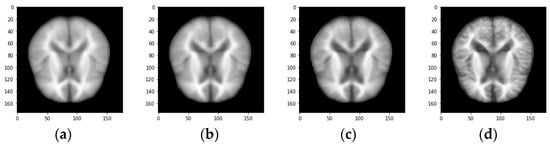

The proposed work aims at the early detection of AD. The data sets play an important role as the training data is needed to train the model for performing the needed actions. Most of the data in the data set used for training the model and data set is also separated into test data. The proposed system executes the algorithm on AD-related datasets obtained from Kaggle with 512 MRI images and the Munich database with 112 PET images; Figure 3 and Figure 4 show the sample image data.

Figure 3.

Sample MRI image demented categories. (a) Non-demented image (b) Very mild demented image (c) Mild demented (d) Moderate demented.